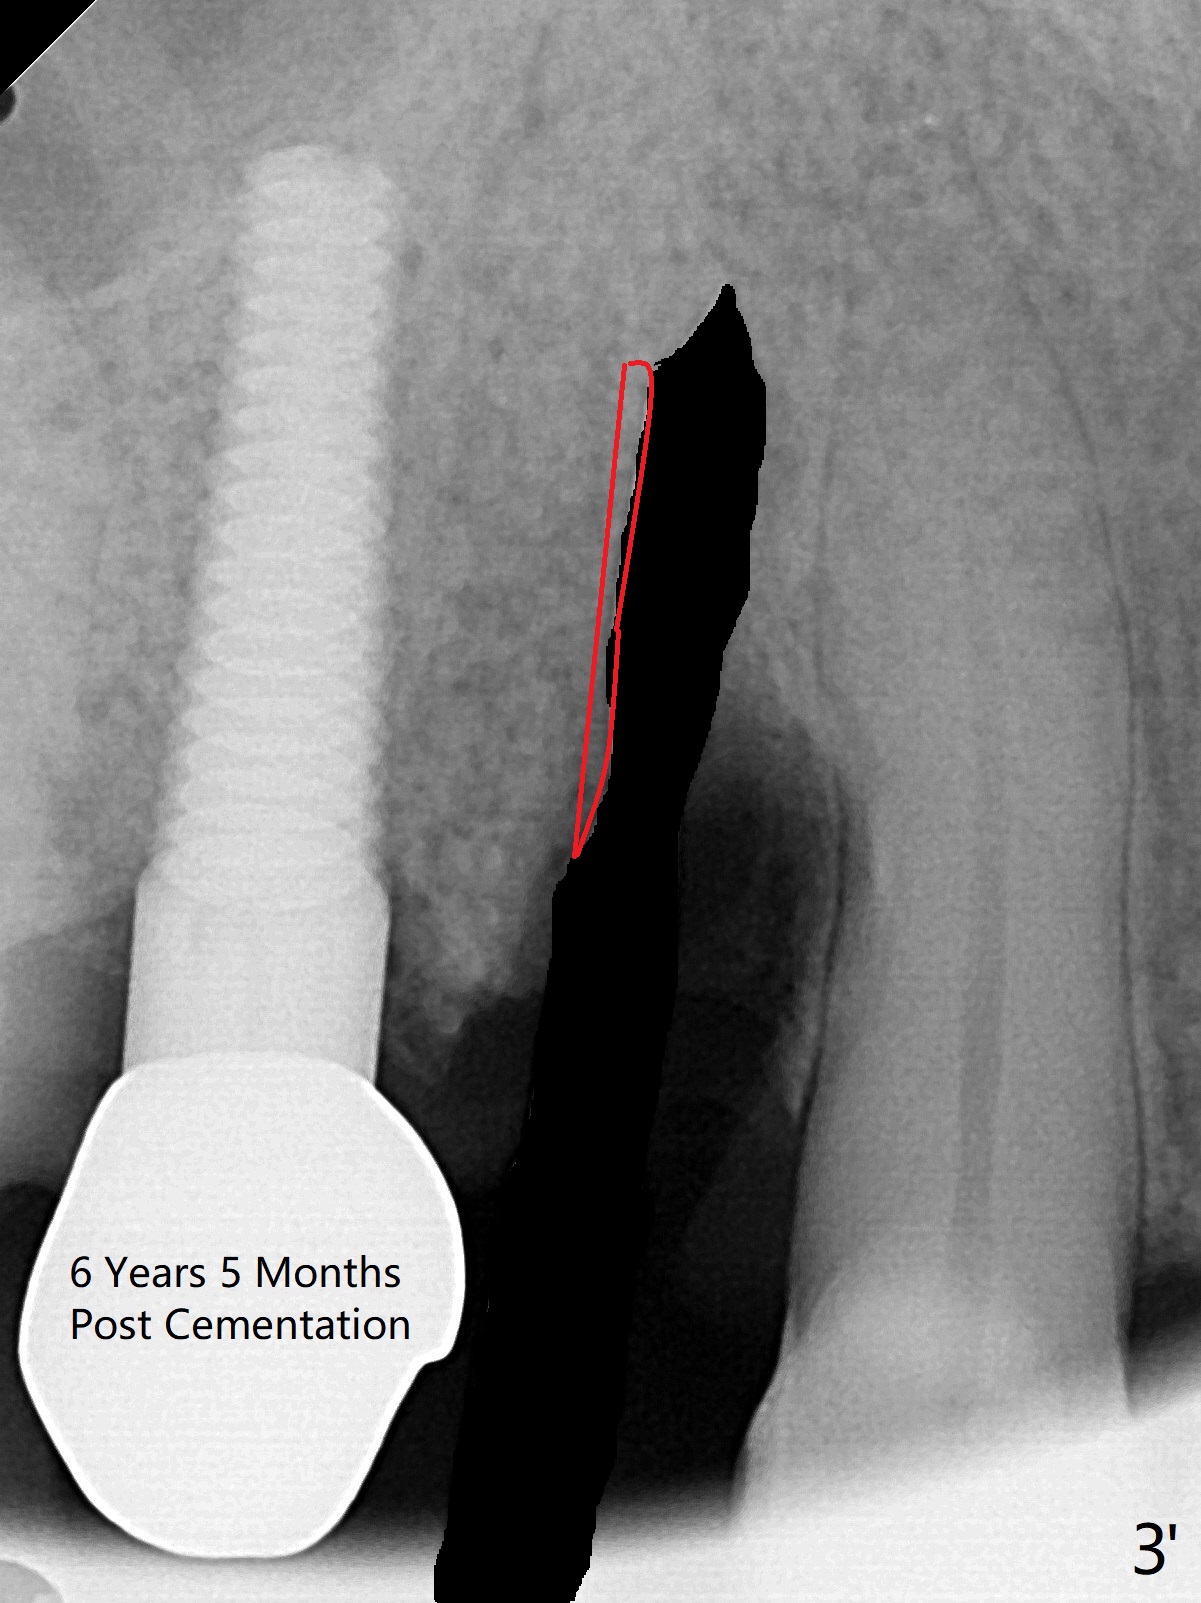

取出钻头(图三’:黑色)后,使用Lindamann 钻头去除远中根尖骨质(红色)。